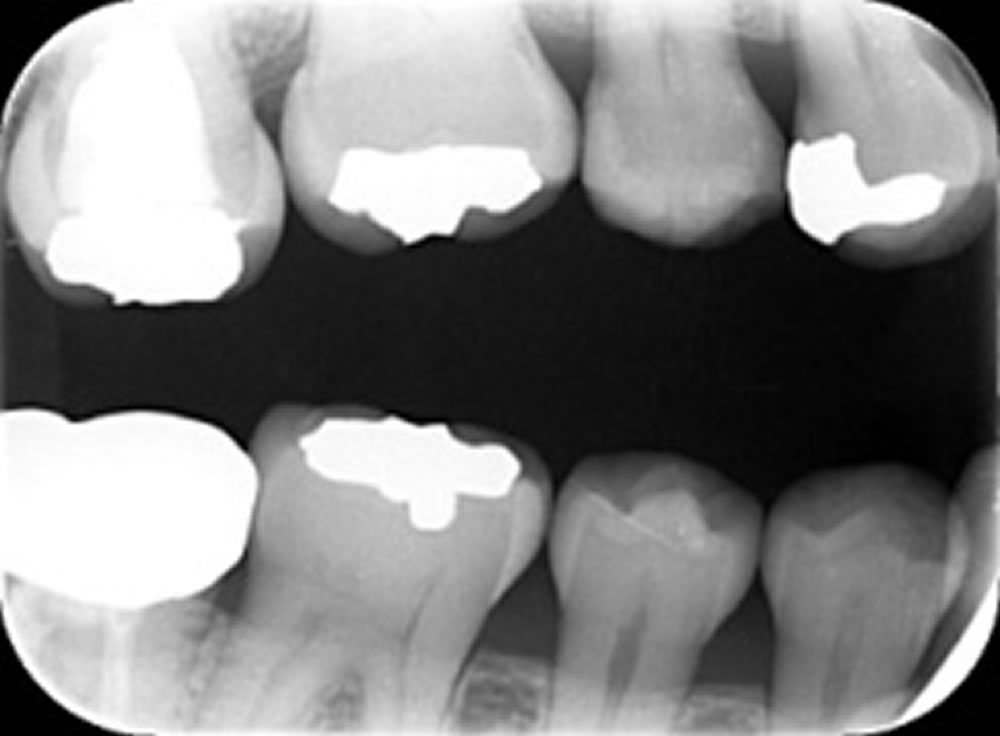

むし歯治療後にセラミックインレーで修復した症例⑤

むし歯治療後にセラミックインレーで修復した症例 こちらの患者さまはコロナ予防で通院を中断していましたが、落ち着いてきたため治療再開を希望され来院されました。 メタルインレーが入っており、不適合のためその下でむし歯が進行し […]